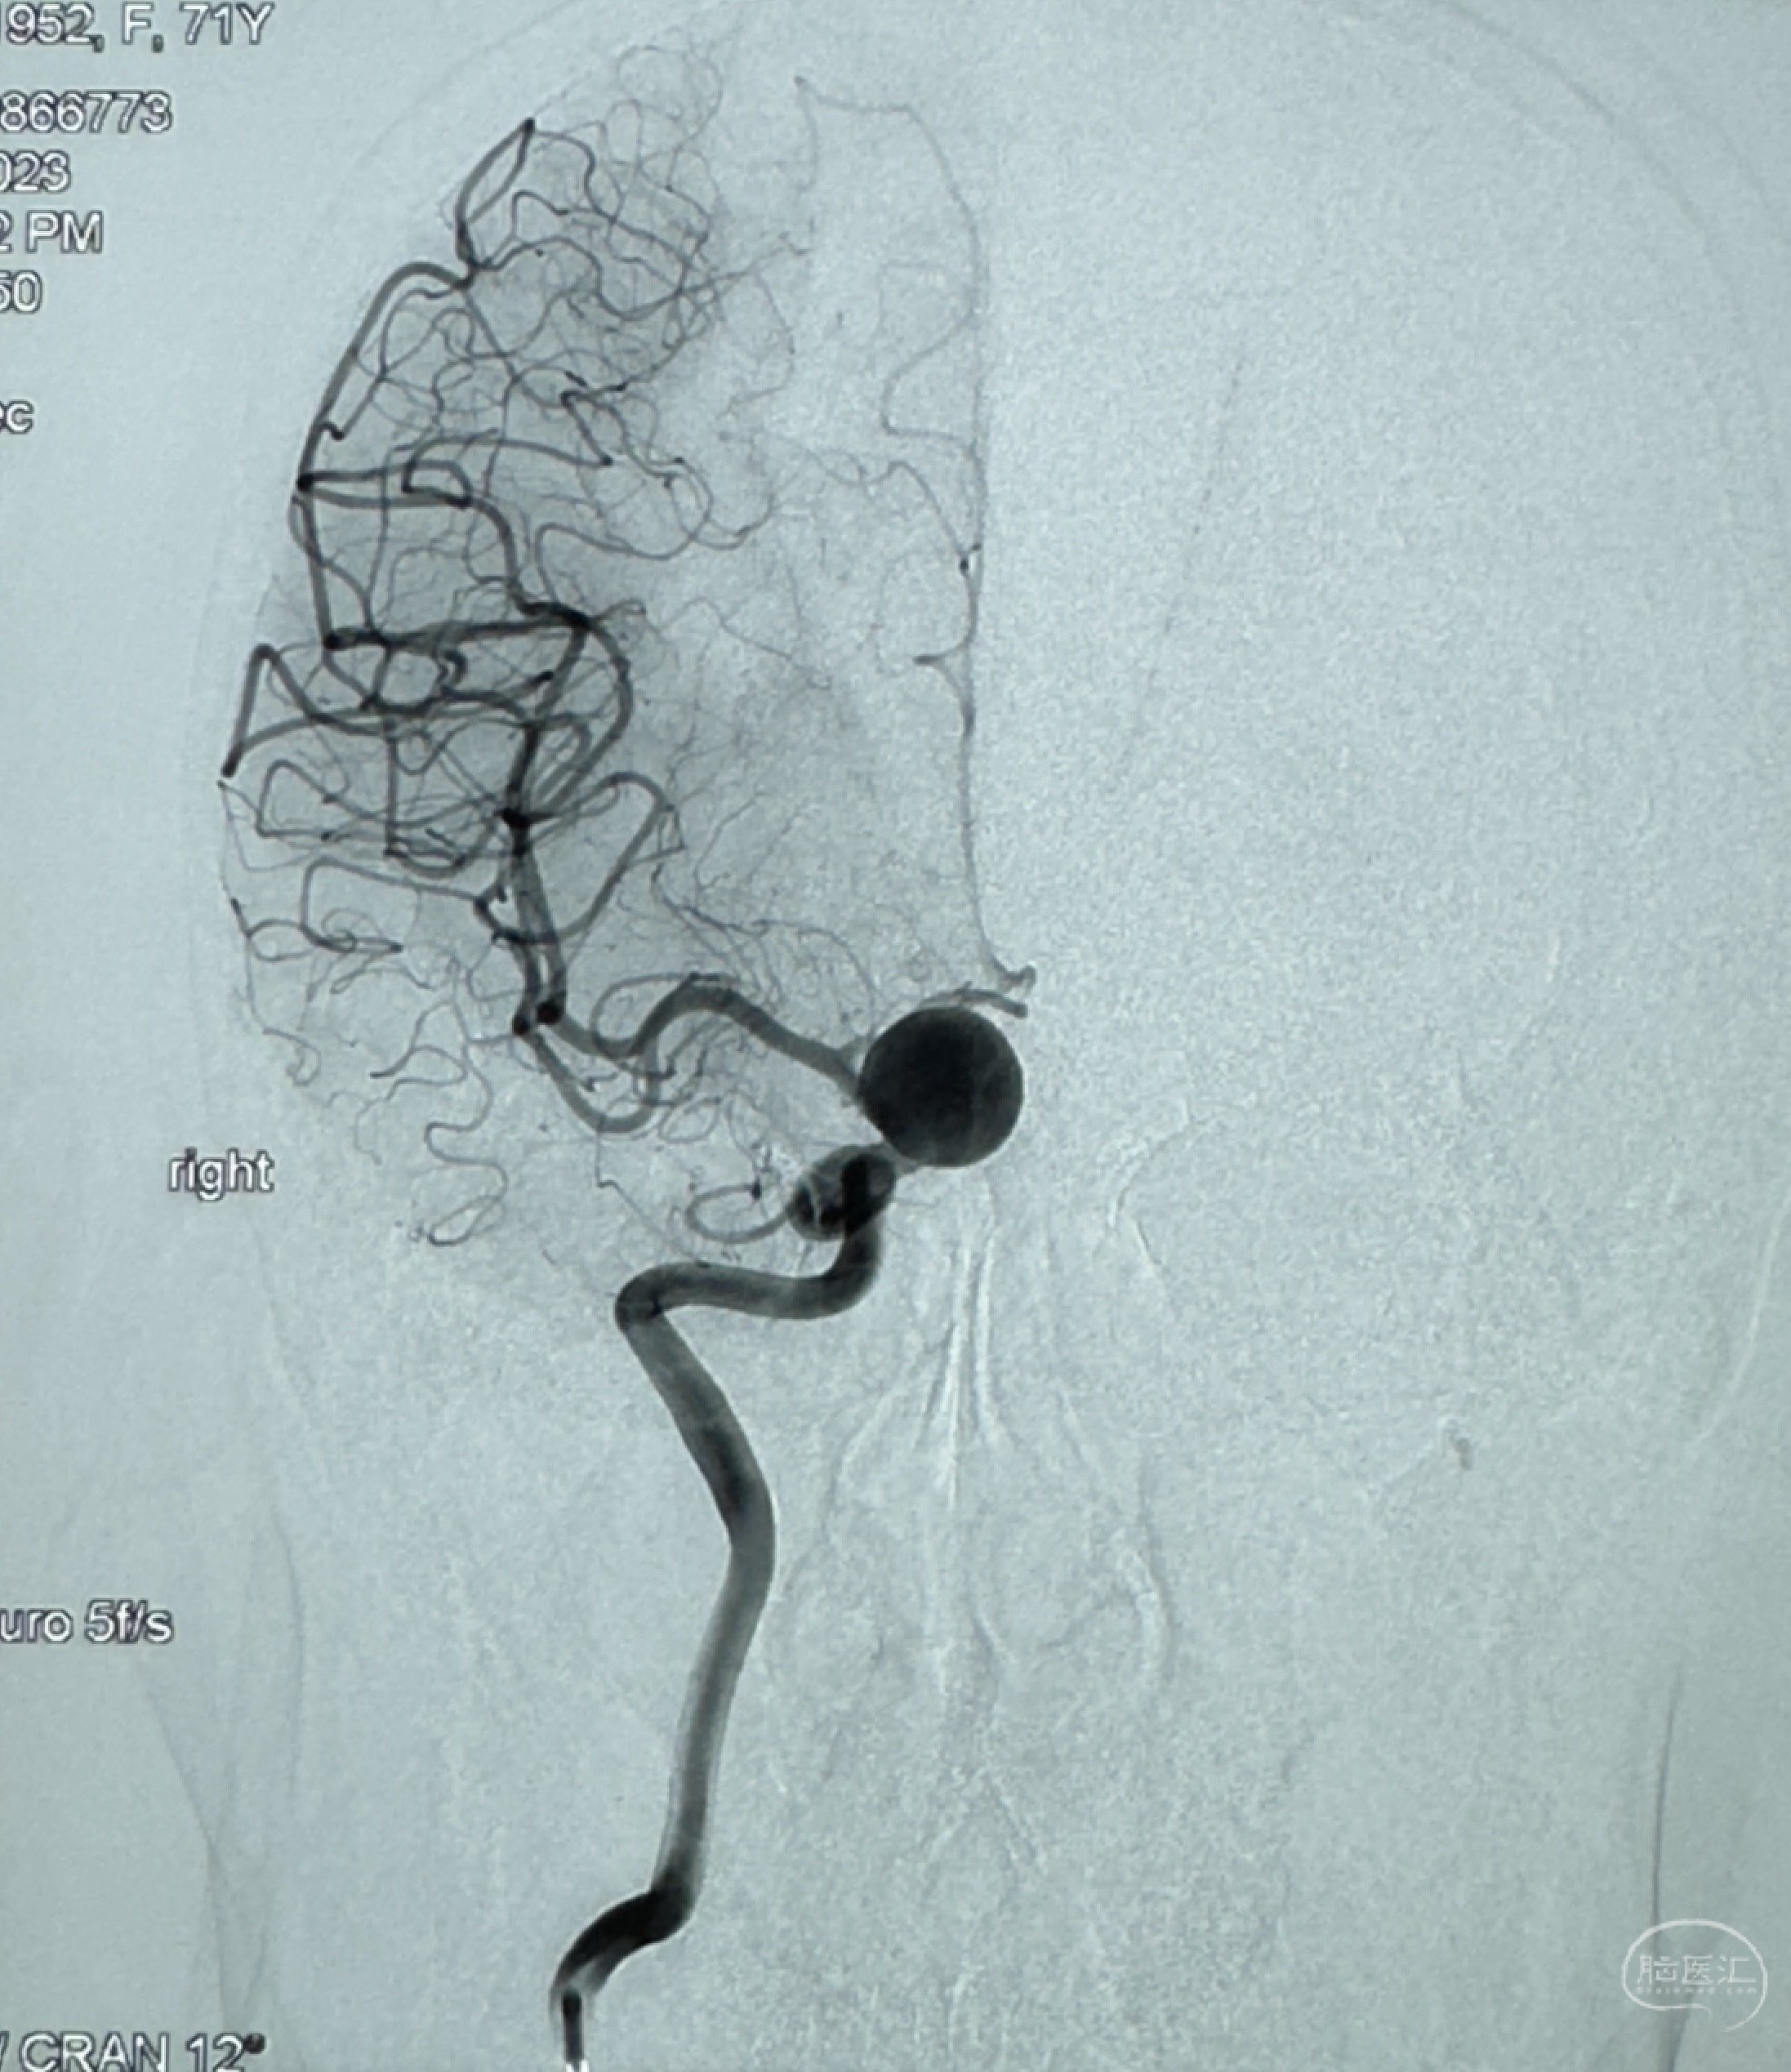

现病史:患者诉2年来反复发作性头痛,顶枕部为主,因自己考虑高血压可能,未予系统检查;患者约20日前无明显诱因下突发剧烈头晕,有天旋地转感,不能睁眼,伴视物模糊;外院查头颅MRI+MRA提示:左侧颈内动脉C6段动脉瘤;遂至复旦大学附属华山医院就诊,于2023-12-08行全脑血管造影提示:右侧颈内动脉C6段动脉瘤,瘤颈6.68mm,动脉瘤大小13.28*12.34mm,建议行密网支架辅助栓塞术治疗,因缺乏相关材料遂出院。现患者仍有顶枕部头痛不适,为求进一步诊疗脑血管病变至我科就诊,收治入院。

2023-12-08 复旦大学附属华山医院 全脑血管造影:右侧颈内动脉C6段动脉瘤,瘤颈6.68mm,动脉瘤大小13.28*12.34mm

2023-12-08外院DSA:右侧颈眼动脉瘤,约13*12mm大小,压颈试验显示左右向及后向前代偿可